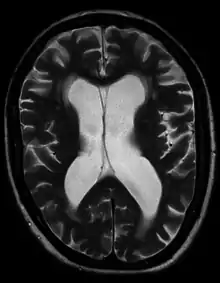

Hydrocephalus ex vacuo from vascular dementia as seen on MRI

• Hydrocephalus ex vacuo also refers to an enlargement of cerebral ventricles and subarachnoid spaces, and is usually due to brain atrophy (as it occurs in dementias), post-traumatic brain injuries, and even in some psychiatric disorders, such as schizophrenia.[33] As opposed to hydrocephalus, this is a compensatory enlargement of the CSF-spaces in response to brain parenchyma loss; it is not the result of increased CSF pressure.[33]